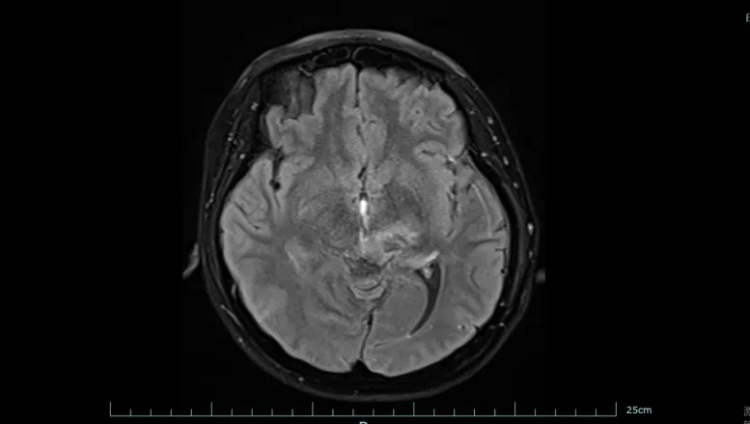

图一为治疗前,图二为治疗后

好在经过系统治疗,黄女士的肿瘤明显缩小,病情得到有效控制。目前,她已回归正常生活和工作,生活质量显著改善。